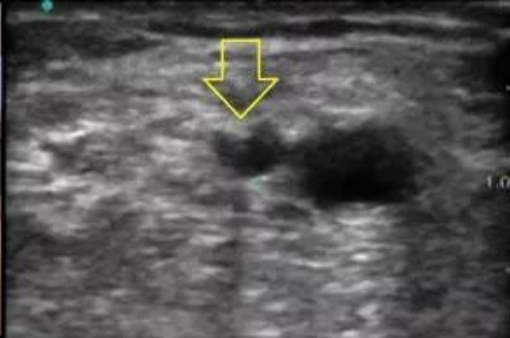

2.2 新建内瘘的成熟与穿刺点确认,运用超声技术可以更方便的了解内瘘成熟情况与可穿刺段血管的情况!

第二步,根据触诊和超声检查情况,为患者绘制AVF穿刺计划图,注明狭窄、禁穿刺区域、静脉保护区域等;也要借助超声技术。